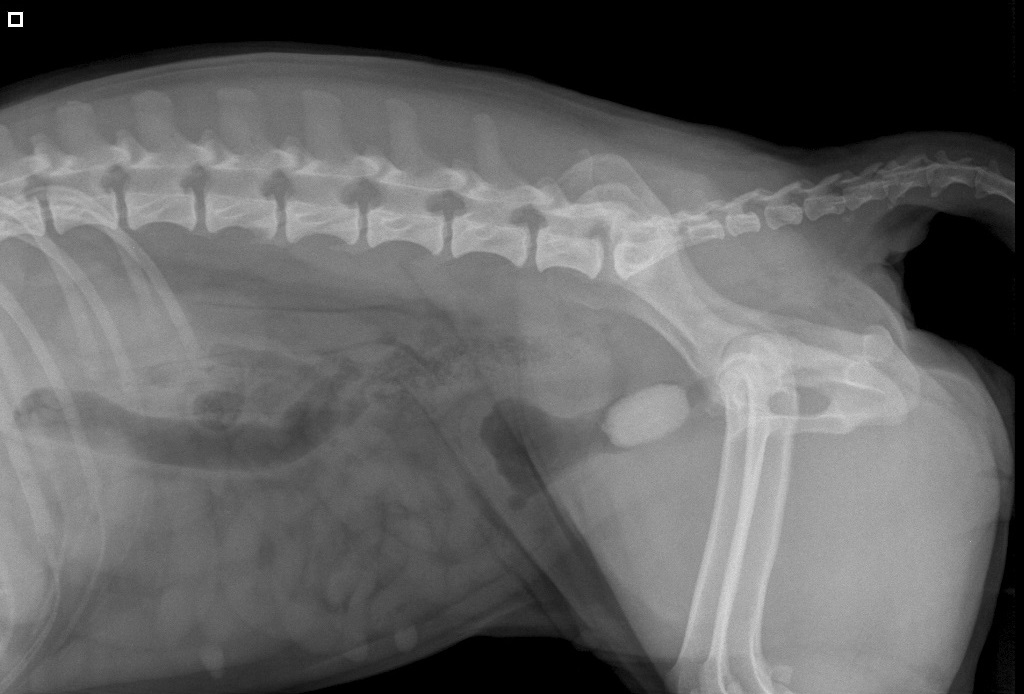

Röntgenfoto van Yvi:

A: blaas

B: de steen